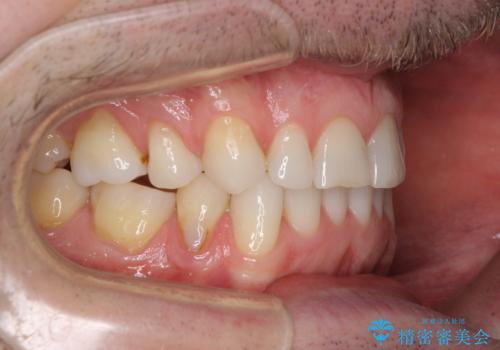

- 上下前歯の叢生を気にして来院された患者様です。

抜歯矯正をした後戻りということで、歯列不正はそれほど大きくなかったため、インビザライン・ライトを用いて矯正治療を行うこととしました。

前歯のデコボコが残っており、シミュレーション通りに動いていない部分がありましたが、再矯正であることやご本人の満足いくところまでデコボコが改善されたとのことで、治療を終了することとしました。